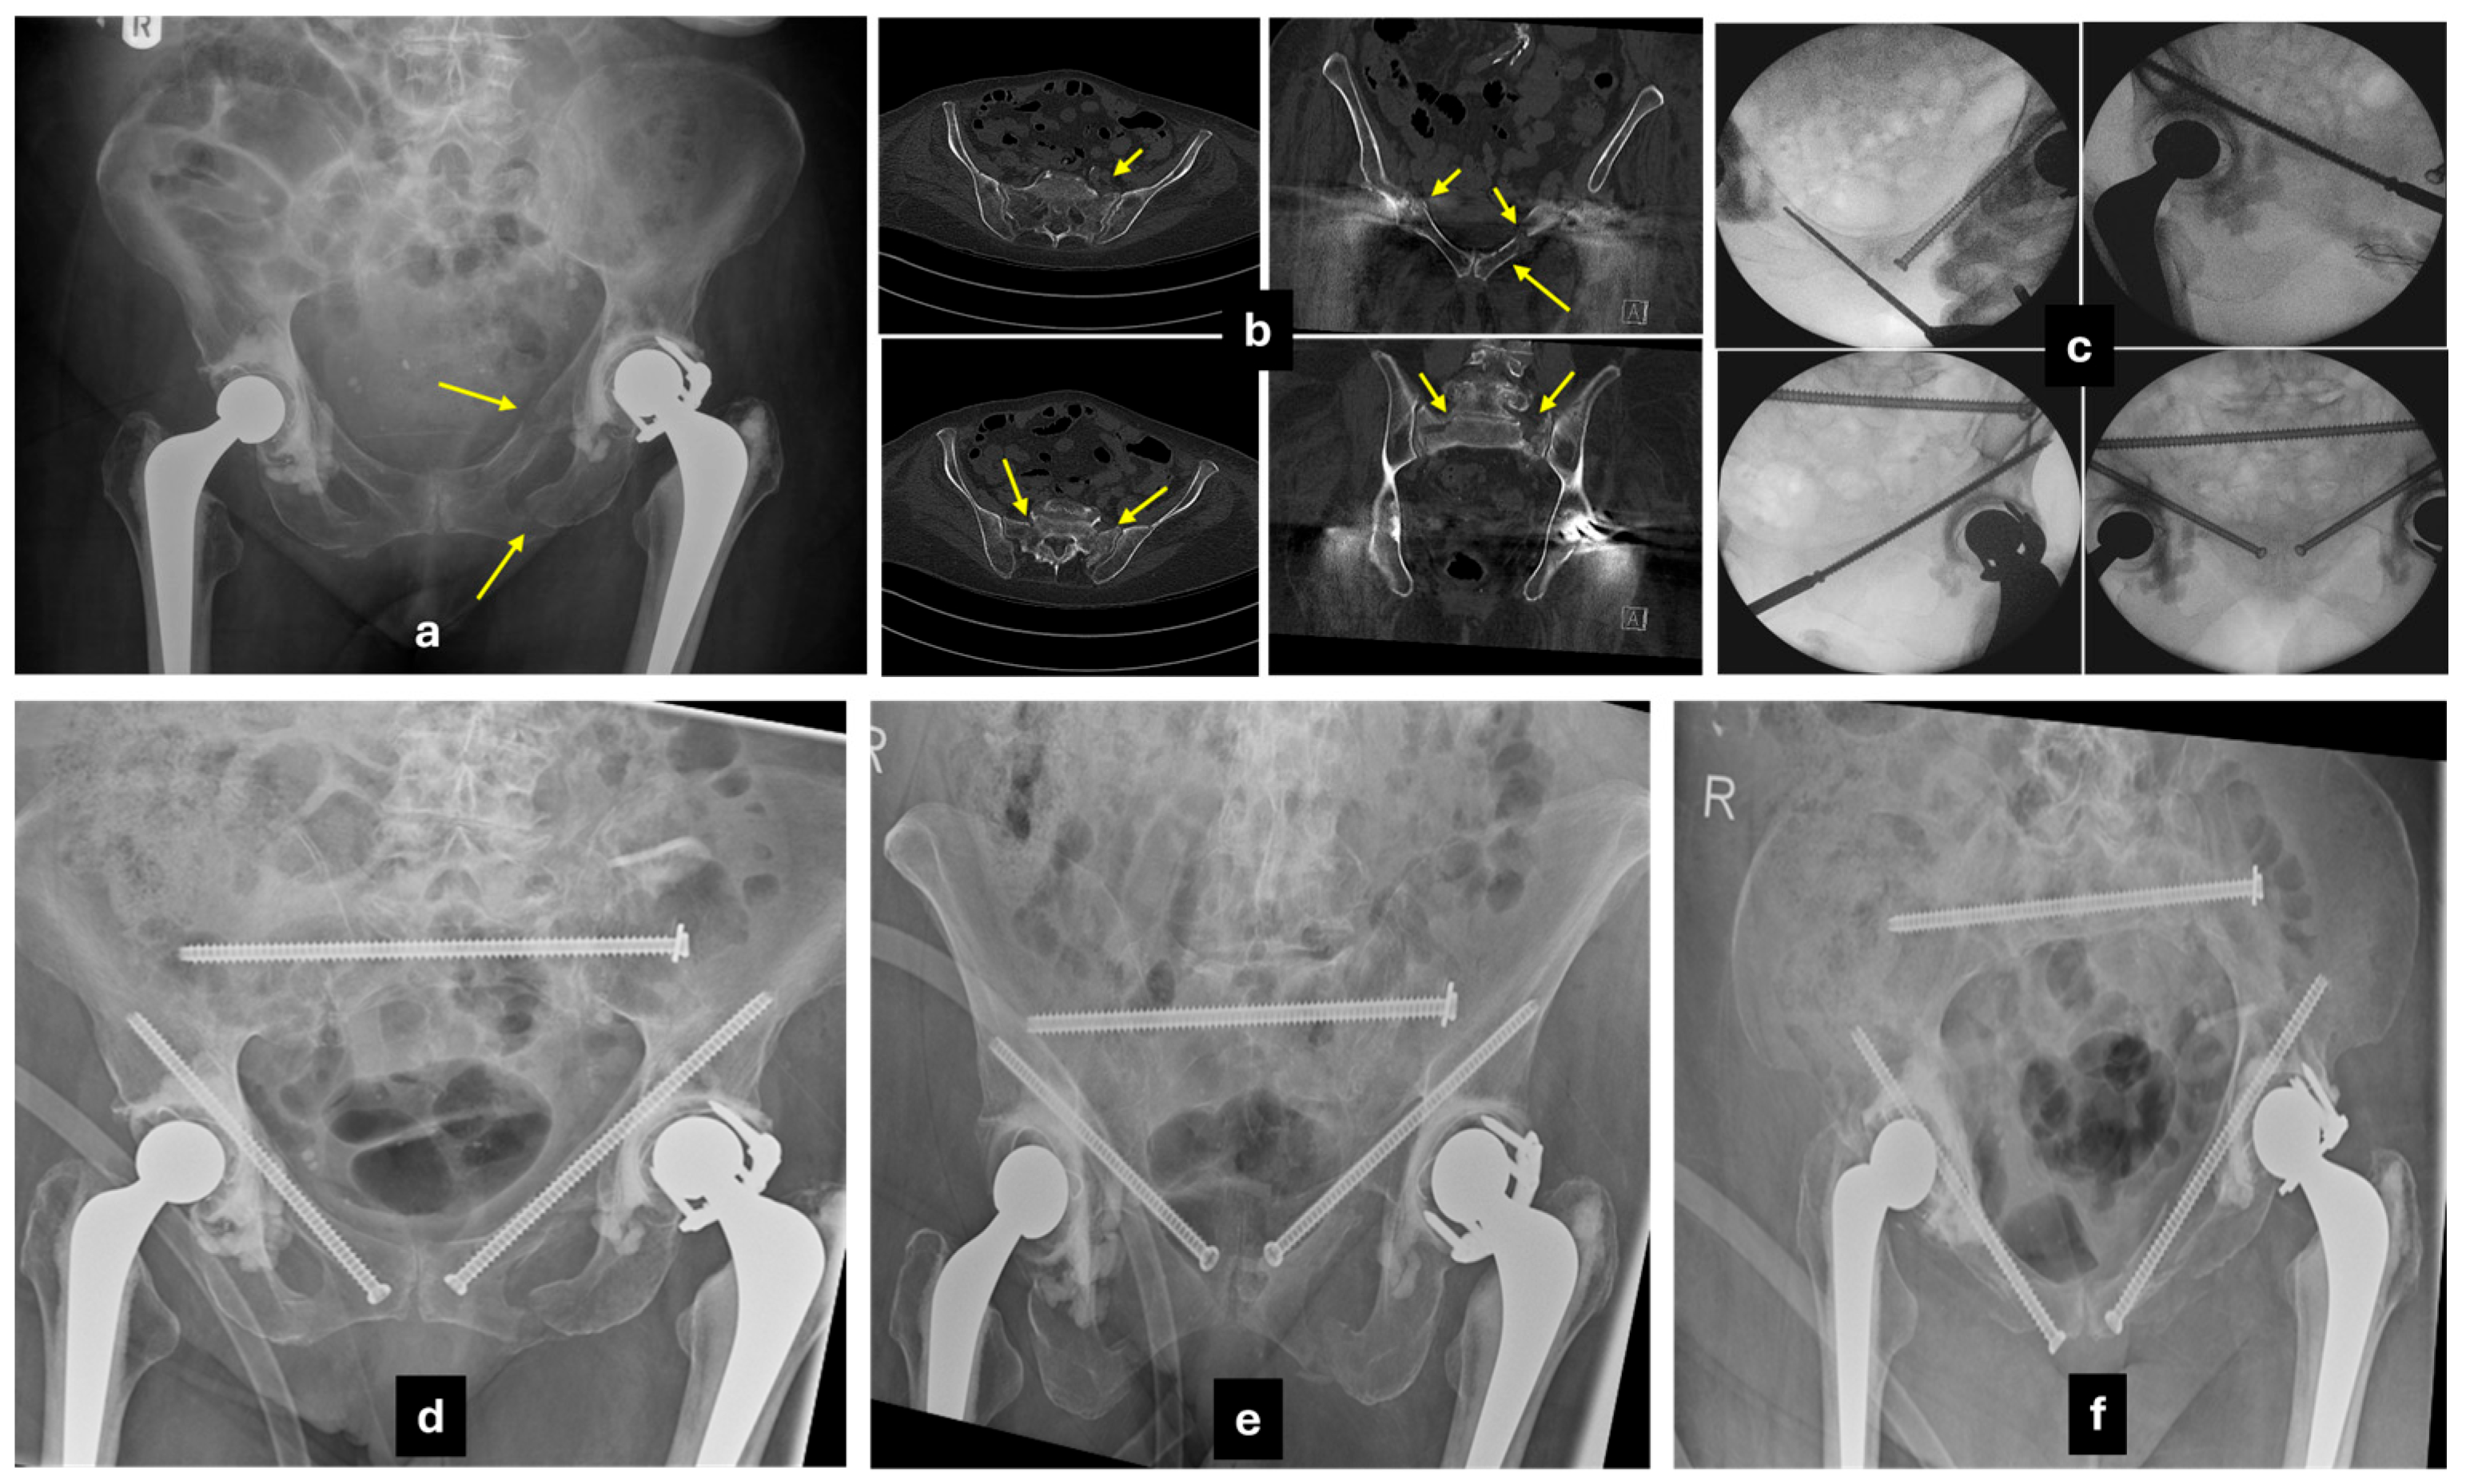

5.4. Anterior Fixation

5.4.1. Conventional Anterior Plating

5.4.2. Percutaneous Screw Fixation

5.4.3. External Fixator